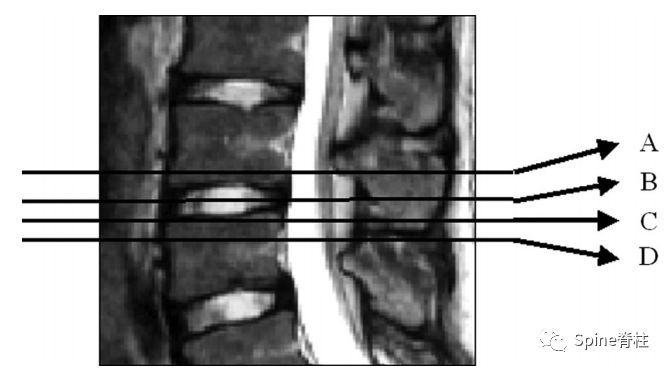

示意图总结了临床和尸体研究的矢状位MRI结果:

A=峡部正常,无硬化,从上至下小关节骨髓信号正常

B=部分小关节切除

C=正常但硬化的峡部,骨髓信号中断

D=峡部裂伴硬化边缘,无间隙

E=S1上关节突和L5椎弓根的部分容积成像疑似峡部断裂

F=峡部裂伴间隙

G=具有弥漫性异常骨髓信号(对角线)和邻近软组织肿块(虚线区域)的转移性疾病

H=纤细、硬化的峡部,小关节退变伴骨髓信号异常(对角线) PMID: 2783509

因此,Sairyo教授也提出,对于青少年腰痛患者行MRI检查时,在传统椎间盘层面的基础上(A-C线),多加一个经椎弓根层面(D线)。因为,A-C线椎间盘层面可很好看出青少年腰椎间盘突出和腰椎椎体后缘离断症,而D线经椎弓根层面可以早期诊断出腰椎峡部裂和腰椎椎弓根损伤。